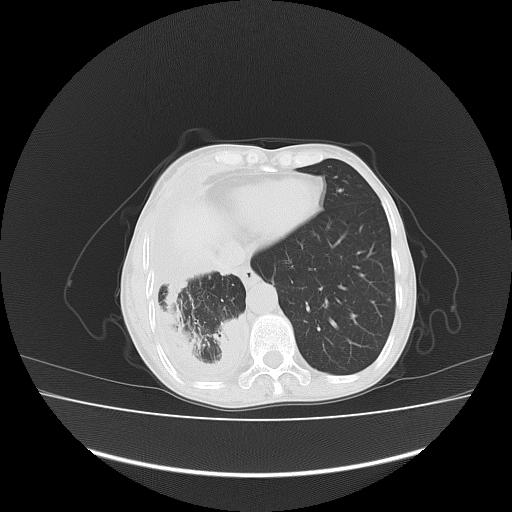

可见多发肺内病灶,且胸膜病灶较多有圆球状而非丘状,多考虑胸膜转移瘤伴胸腔积液,右侧胸廓缩小固定,且部分病灶呈丘状,尚不除外恶性胸膜间皮瘤伴肺内转移

右侧胸膜增厚,局部呈结节状增厚,右侧胸腔少量积液。双肺未见确切肿块影。纵隔未见淋巴结肿大。气管、支气管通畅。考虑右侧胸膜间皮瘤(恶性?)可能性大。不除外癌性胸膜炎。

恶性胸膜间皮瘤伴肺内转移可能性大;或胸膜、肺内均为转移瘤,左肺下叶亦见多发小结节影。

右侧胸廓塌陷,右侧胸膜广泛增厚并见多发胸膜结节,右侧少量胸腔积液并包裹。

右侧广泛胸膜增厚,局部呈结节状增厚,右侧胸腔少量积液。双肺未见确切肿块影。纵隔未见淋巴结肿大。气管、支气管通畅。考虑右侧胸膜间皮瘤(恶性?)可能性大。支持!

右胸腔结节均考虑来自胸膜(部分来源于叶裂),考虑胸膜间皮瘤或转移瘤.